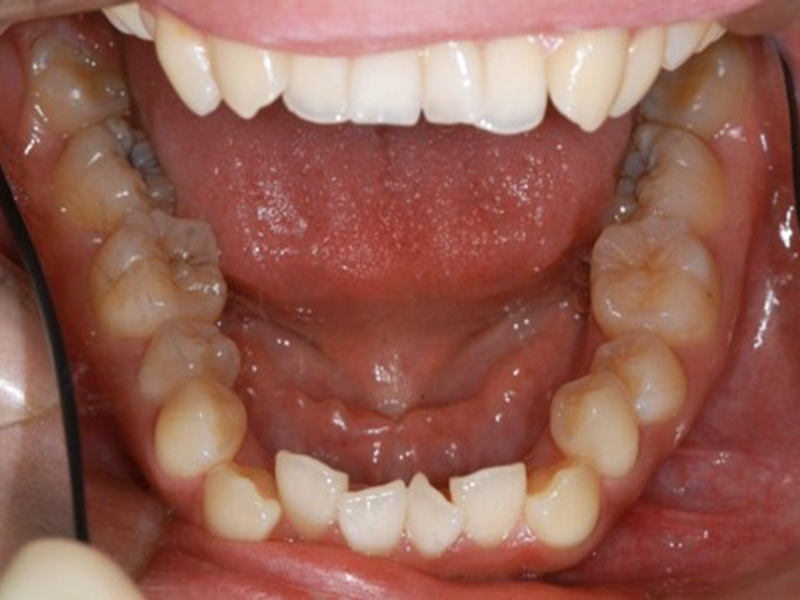

▼ ケース5 下顎前歯部叢生症例

初診時口腔内写真